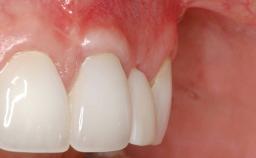

Early Implant Placement, Contour Augmentation, and Autologous Connective-Tissue Graft Using a Tunneling Technique to Replace an Upper Incisor with Generalized Gingival Recession

Variations in soft-tissue volume, evidenced either by an overabundance (Evian and coworkers 1993; Levine and McGuire1997; Dolt and Robbins 1997) or by a deficiency of soft or hard tissue can complicate implant-supported rehabilitations in the esthetic zone (Lorenzana 2008; Lorenzana and coworkers 2009). The present case illustrates the replacement of a failing upper left lateral incisor complicated by generalized severe gingival recession in the esthetic zone.

| Soft Tissue Grafting | Simultaneous |